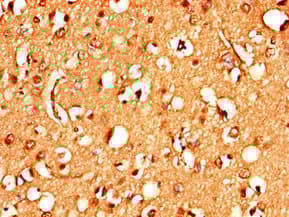

Anti-STIM2 antibody(ab223033)

Rabbit Polyclonal STIM2 antibody. Suitable for WB, IHC-P and reacts with Human, Mouse samples. Immunogen corresponding to Recombinant Fragment Protein within Human Stromal interaction molecule 2 aa 450-700.

Applications IHC-P, WB

Species Reactivity Human, Mouse